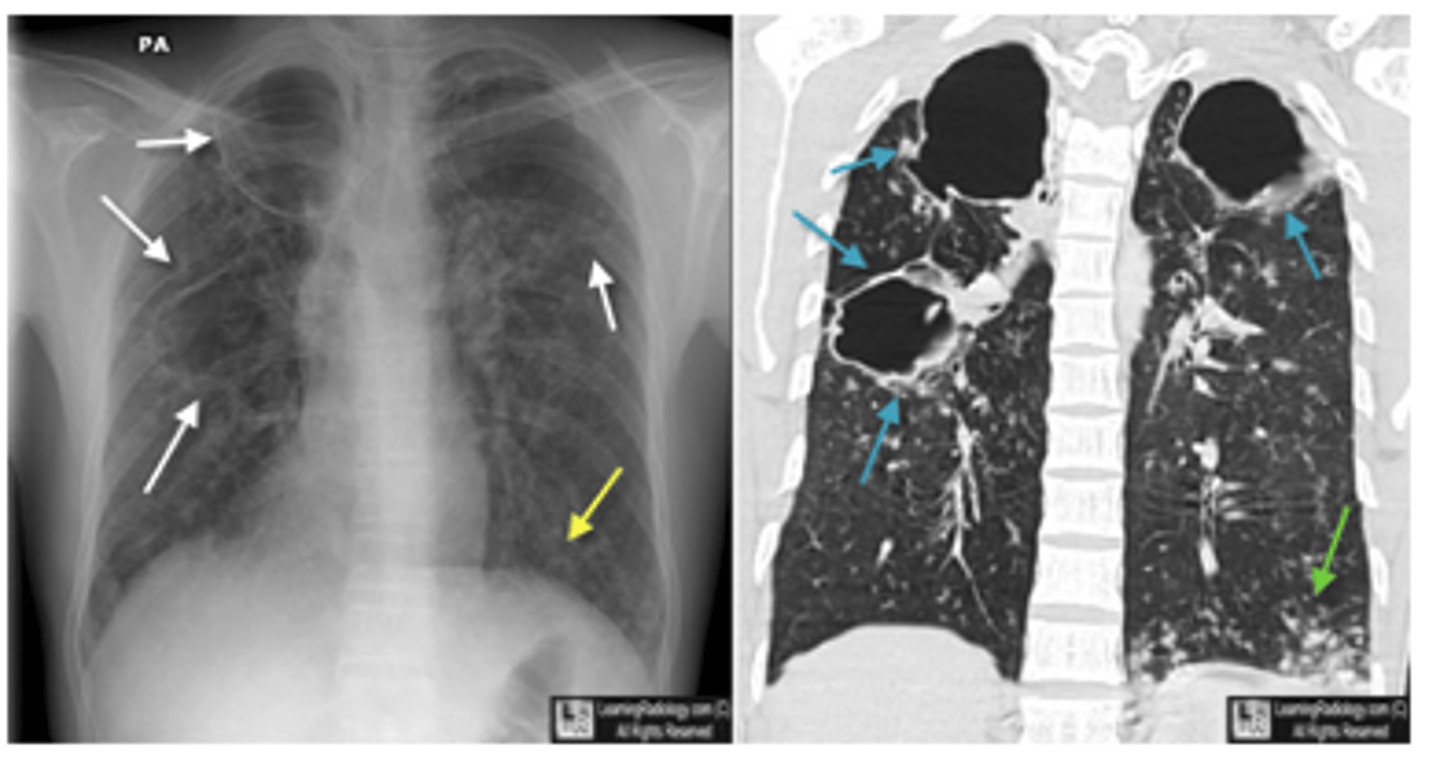

Common x-ray finding of military TB. What makes military TB particularly deadly?

diffuse bilateral infiltrates with very small nodules

-late phase of TB: potentially fatal form of the disseminated disease due to the hematogenous spread of tubercle bacilli to the lungs, and other organs.

<p>diffuse bilateral infiltrates with very small nodules</p><p>-late phase of TB: potentially fatal form of the disseminated disease due to the hematogenous spread of tubercle bacilli to the lungs, and other organs.</p>